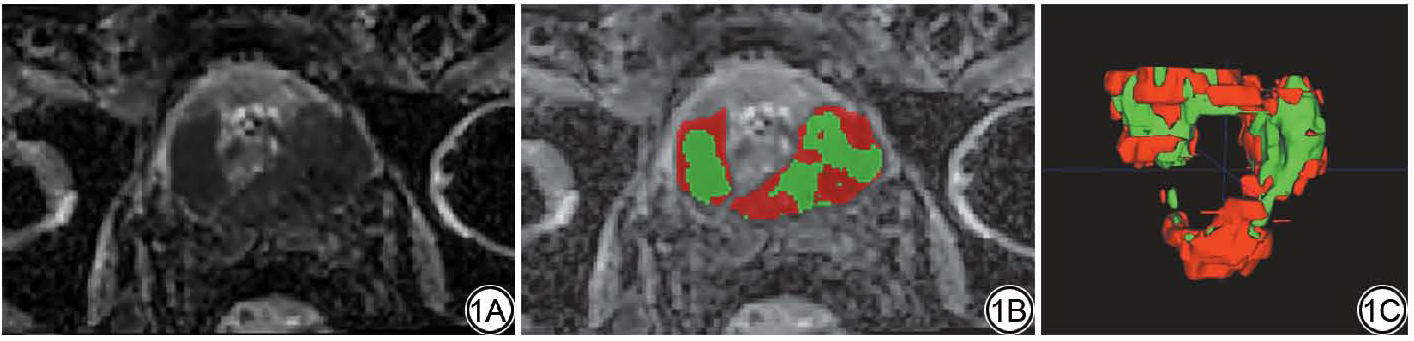

图1  男,70岁,前列腺癌,格里森评分4+4,肿瘤内异质性分数0.91,肿瘤内部异质性较高。1A:表观扩散系数图像;1B:单一层面亚区生成结果,红色代表h1亚区,绿色代表h2亚区;1C:生境亚区空间分布图。

Fig. 1  Male, 70 years old, prostate cancer, Gleason score 4+4, intratumoral heterogeneity score 1A: apparent diffusion coefficient image; 1B: Single-slice subregion generation results, with red representing h1 subregion and green representing h2 subregion; 1C: Habitat subregion distribution map in space.

基于术前bpMRI图像计算的ITHscore在全部患者中表现出广泛的变异范围(0.000~0.943),其均值为0.502±0.279,中位数(四分位距)为0.504(0.209,0.745)(图1)。